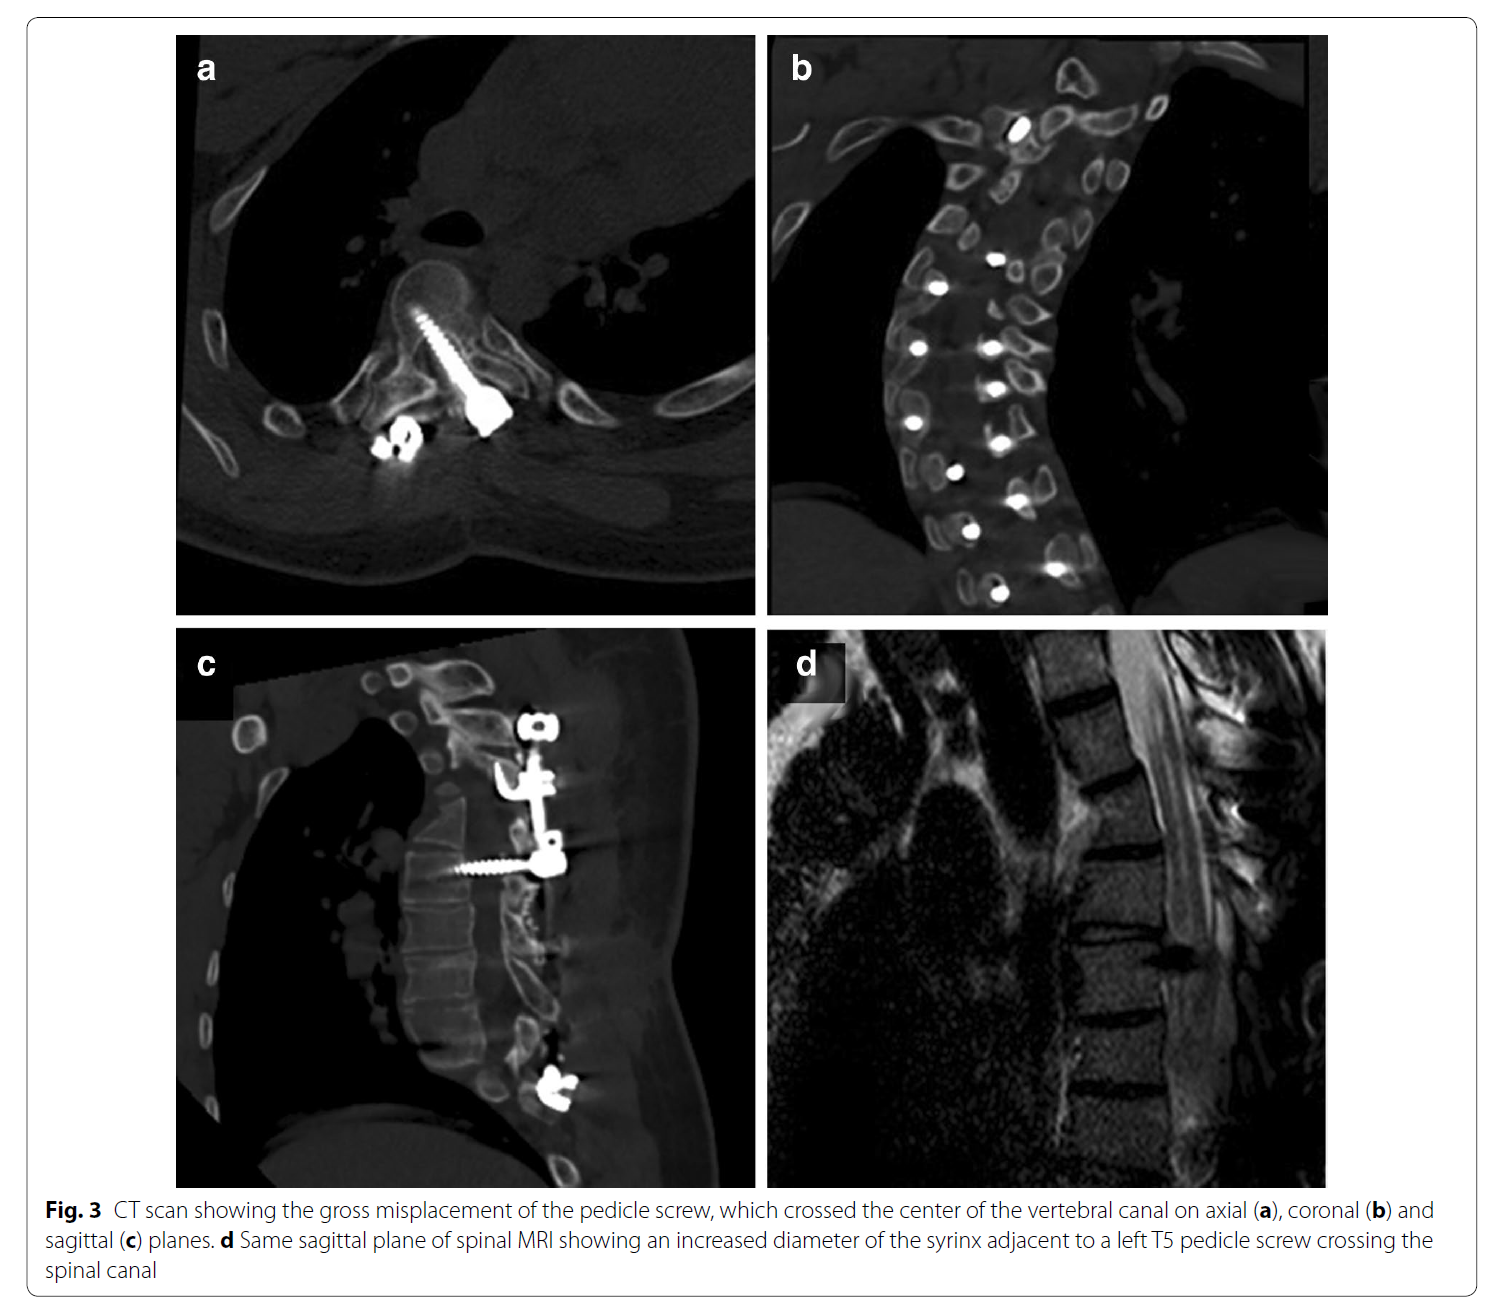

病例报告。19岁男性,脊柱侧凸手术,T2-L1固定,置钉过程SEP正常,矫形上第二根棒时波幅下降90%,唤醒下肢不能活动。减少矫形度数后波幅没有完全恢复,术后病人没有神经症状。6月后病人逐渐出现痉挛性瘫痪表现,下肢肌力4级,肌张力增高,病理征阳性。CT和MRI显示左侧T5椎弓根钉进入椎管。翻修手术取出左侧T5钉子,3月后脊髓症状消失。

评论。此例病人T5左侧是凹侧,脊髓也应该靠近左侧的凹侧,左侧钉子完全进入椎管,理论上钉子应该横断了脊髓,而不只是压迫。但病人没有神经症状,有些不好理解。虽然有矢状位MRI,但没有轴位片,文中钉子和脊髓的关系实际上没有明确。最引起读者好奇心的地方没有交待,作者和reviewer都该面壁。但无论如何,还是长了见识,以后置钉应该更加谨慎。